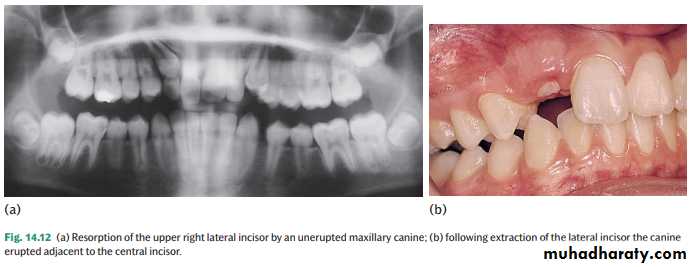

Resorption